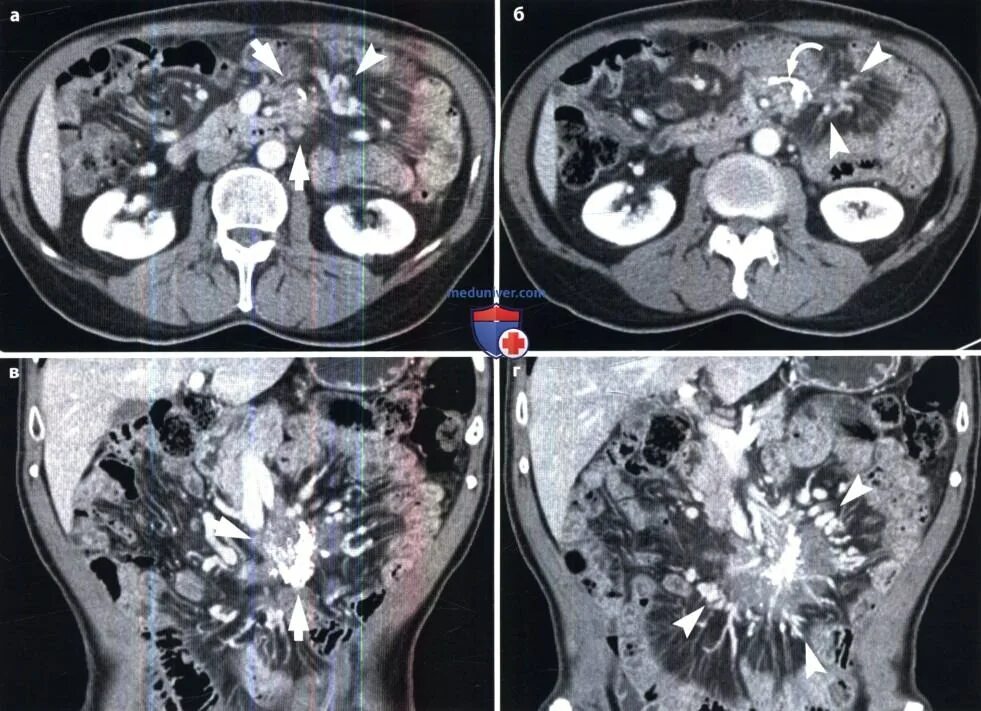

Мскт болюсное контрастирование. болюсное контрастирование при кт. кт с внутривенным болюсным контрастированием. болюсное контрастное усиление при кт.Компьютерная томография с болюсным контрастированием. кт с болюсным контрастированием что это. мскт болюсное контрастирование. спиральная компьютерная томография с болюсным контрастированием.Отечная форма панкреатита кт. кт признаки острого панкреатита. острый панкреатит кт с контрастированием. кт картина панкреонекроза.Томография с болюсным контрастированиемБолюсное контрастирование при кт брюшной полости. хемодектома забрюшинного пространства. кт с контрастом брюшной полости с болюсным контрастированием. эхинококкоз кт с контрастированием.Фазы контрастирования печени мрт. динамическое контрастирование печени мрт. фазы контрастирования при кт. кт с контрастом брюшной полости с болюсным контрастированием.Компьютерная томография с болюсным контрастированием. кт с болюсным контрастированием что это. кт с внутривенным болюсным контрастированием. болюсное контрастное усиление.Кт с болюсным контрастированием что это. компьютерная томография с болюсным контрастированием. методика болюсного контрастирования. кт обп с болюсным контрастированием.Компьютерная томография с болюсным контрастированием. кт перфузия головного мозга. методика болюсного контрастирования.Томография с болюсным контрастированиемТомография с болюсным контрастированиемКт брюшной полости аорты с контрастированием. кт почек с болюсным контрастированием. контрастирование при кт. контрастное усиление при кт.Томография с болюсным контрастированиемТомография с болюсным контрастированиемТомография с болюсным контрастированиемТомография с болюсным контрастированиемОментит кт. компьютерная томография пжж. кт с болюсным контрастированием панкреатит.Кт с болюсным контрастированием что это. компьютерная томография с болюсным контрастированием. кт брюшной полости презентация.Кт огк с контрастированием. скт огу с контрастированием. кт огк, обп с контрастированием. кт с внутривенным контрастированием.Кт с болюсным контрастированием и пэт кт. контрастное усиление при кт обп. кт с болюсным контрастированием что это.Томография с болюсным контрастированиемТомография с болюсным контрастированиемТомография с болюсным контрастированиемТомография с болюсным контрастированиемТомография с болюсным контрастированиемТомография с болюсным контрастированиемТомография с болюсным контрастированиемТомография с болюсным контрастированиемТомография с болюсным контрастированиемТомография с болюсным контрастированиемТомография с болюсным контрастированиемТомограмма брюшной полости кт. кт обп норма. кт брюшной полости и забрюшинного пространства. кт обп с контрастированием норма.Томография с болюсным контрастированиемКт с контрастированием почек онкология. кт ангиография почечных артерий. кт почек с контрастированием норма.Спиральный компьютерный томограф с болюсом. компьютерная томография с болюсным контрастированием. кт с внутривенным болюсным контрастированием.Кт головного мозга с контрастированием. мрт головного мозга с контрастом. кт с контрастом.Мрт обп с контрастом. мрт исследование с контрастированием. кт с контрастированием. кт брюшной полости с контрастом.Томография с болюсным контрастированиемКт с контрастированием брюшной полости контрастированием органов. кт почек с болюсным контрастированием. кт обп с болюсным контрастированием. томограмма брюшной полости кт.Кт ангиограмма. кт ангиография с контрастированием. кт-ангиография артерий нижних конечностей.